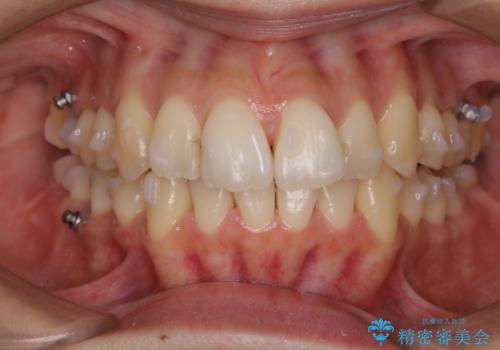

この方は、インビザラインの矯正中の患者様で、奥歯のアタッチメント付近に着色が多く付いていました。

軽度な着色であれば30分コースで全体をクリーニングすることが可能です。